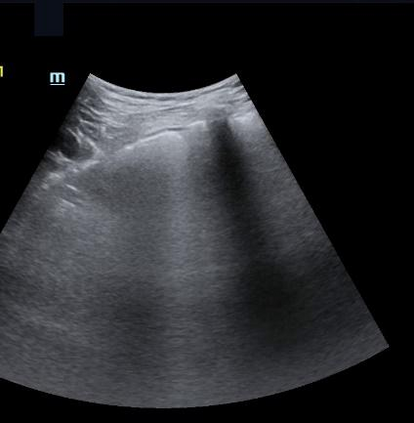

Most deep neural networks (DNNs) based ultrasound (US) medical image analysis models use pretrained backbones (e.g., ImageNet) for better model generalization. However, the domain gap between natural and medical images causes an inevitable performance bottleneck. To alleviate this problem, an US dataset named US-4 is constructed for direct pretraining on the same domain. It contains over 23,000 images from four US video sub-datasets. To learn robust features from US-4, we propose an US semi-supervised contrastive learning method, named USCL, for pretraining. In order to avoid high similarities between negative pairs as well as mine abundant visual features from limited US videos, USCL adopts a sample pair generation method to enrich the feature involved in a single step of contrastive optimization. Extensive experiments on several downstream tasks show the superiority of USCL pretraining against ImageNet pretraining and other state-of-the-art (SOTA) pretraining approaches. In particular, USCL pretrained backbone achieves fine-tuning accuracy of over 94% on POCUS dataset, which is 10% higher than 84% of the ImageNet pretrained model. The source codes of this work are available at https://github.com/983632847/USCL.